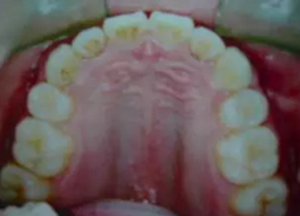

答二、拔牙以后的牙縫在矯治器的作用下,是完全可以關(guān)閉的。

2.png

一般來說,拔牙以后的牙縫可以被兩個方面的牙齒移動所關(guān)閉,一個是前面不齊、前突的牙齒向拔牙間隙移動,占據(jù)部分拔牙間隙,還有就是后面的大牙也可以向關(guān)(拔牙間隙)移動,這樣就可以關(guān)閉了這個間隙。